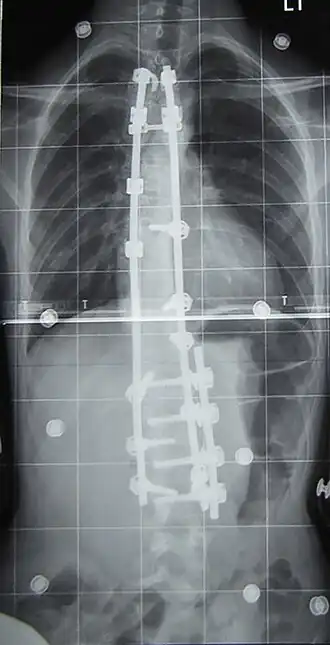

Wanneer de uiteindelijke bocht naar men verwacht boven de 40 à 45 graden uit komt, wordt in principe een operatie geadviseerd. Hierbij heeft men de keuze tussen benadering van de voorzijde (anterior fusion) en van de achterzijde (posterior fusion). Belangrijk is dat niet alleen door het laten versmelten van wervels de zijdelingse bocht wordt gestabiliseerd, maar dat ook de rotatie wordt tegengegaan. Daarom wordt een pen (een zogenaamde Harringtonstaaf, genoemd naar de Amerikaanse orthopeed Paul Harrington) operatief langs de wervels geplaatst en op meerdere plaatsen vastgezet.

-

Voor operatie -

Na operatie